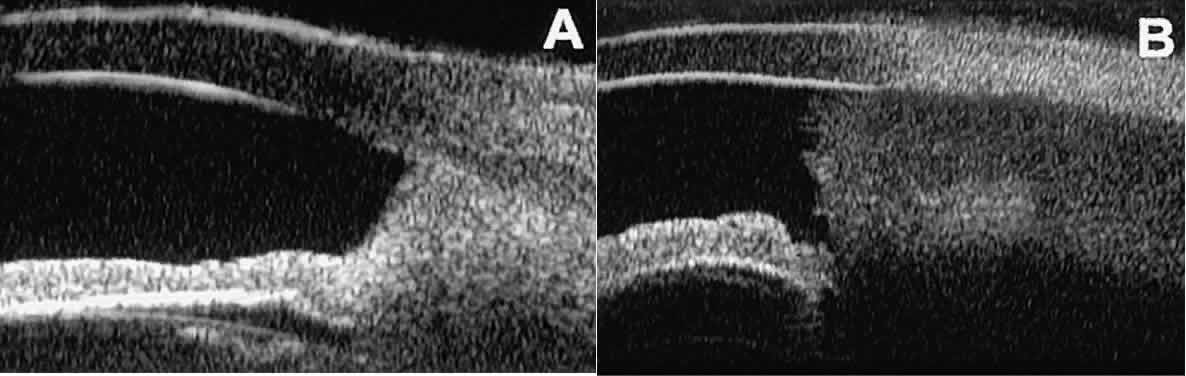

In eyes with a narrow angle, UBM shows the extent of angle closure, reveals

the depth of the anterior and posterior chambers, and identifies

pathologic processes pushing the lens and iris forward (Fig. 11).2–4,8 UBM has been able to differentiate between primary angle closure (i.e., cases of angle closure without additional pathology responsible for the

anterior lens-iris displacement [see Fig. 11A] and secondary angle closure due to processes such as lens swelling

and dislocation (see Fig. 11B), massive hemorrhagic retinal detachment pushing the lens and iris anteriorly (see Fig. 11C), and multiple neuroepithelial cysts of the iridociliary sulcus (see Fig. 11D).  Fig. 11. Angle configuration in eyes with angle-closure glaucoma. A. Primary angle-closure glaucoma with anterior displacement of lens and

subretinal blood is evident in the lower right corner of the photograph. D. Angle closure secondary to multiple peripheral iris cysts. Fig. 11. Angle configuration in eyes with angle-closure glaucoma. A. Primary angle-closure glaucoma with anterior displacement of lens and

iris. B. Angle closure secondary to swollen, cataractous lens (phakomorphic angle

closure). C. Angle closure secondary to massive hemorrhagic retinal detachment; the

subretinal blood is evident in the lower right corner of the photograph. D. Angle closure secondary to multiple peripheral iris cysts.